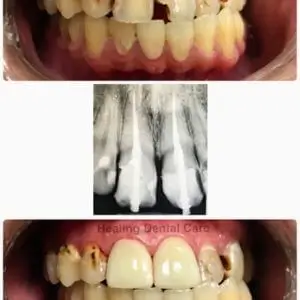

Healing Dental Care – Los Angeles provides gentle, comprehensive dental treatments with a focus on comfort and wellness. Their dedicated team is committed to restoring and maintaining healthy, beautiful smiles.

Teeth Whitening

Dental Fillings

Dental Implants